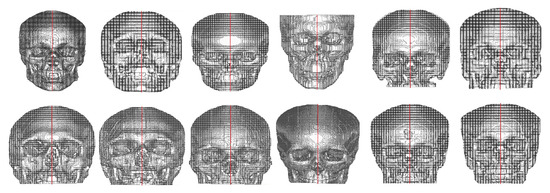

After the alignment, for each of the 101 images, a set of 441 images with inclination angles from −5° to 5°, with 0.5° increments, along the coronal and transverse planes was created. In total, 44541 images were created and were divided into 21 labels. These labels represented the 0.5° of variation in the coronal and transverse planes from −5° to 5°, as shown in Figure 5.

Figure 5.

Examples of images rotated in the coronal and transverse planes where parentheses represents (coronal, sagittal), respectively.